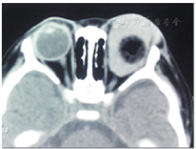

术后眶内出血2例,均发生于术后3 d内,表现为眶内容受挤压脱出于睑裂之外,睑裂不能闭合,其中1例行眼眶CT(图3)示义眼台周围有高密度影,两例患者均给予静点甘露醇脱水,静点地塞米松磷酸钠减轻眶部水肿,结膜囊涂红霉素眼膏,加压包扎后逐渐好转。

眶内出血是一种较严重的并发症。它表现为术后患者眼部胀痛不适,查体可见眼眶内容向外突出,甚至达结膜囊外,结膜暴露。CT可显示义眼台周围有大量高密度影,考虑为渗出的血液,结膜向前移位,脱出睑裂之外。我们分析其原因可能与患者活动造成视神经断端的眼动脉或视网膜中央动脉再次破裂出血所致。两例患者均采用保守治疗,给予止血,脱水及减轻眶压等保守方法痊愈。